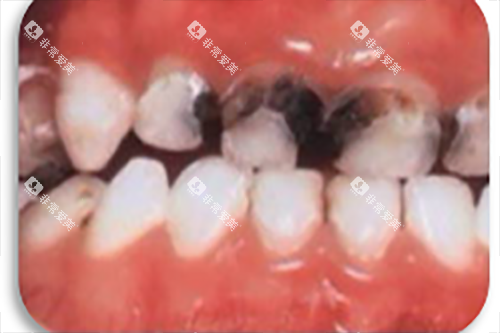

补牙是治疗龋齿的常见方法,能够防止龋齿进一步发展。

在金华地区,补牙的收费价格与补牙材料和龋齿的程度有关。

常见的补牙材料有玻璃材料和树脂材料。

玻璃材料材料价格相对较低,每颗牙齿的补牙费用大约在100 - 300元。

树脂材料的美观度和耐磨性较好,是目前使用较多的补牙材料,其价格也会稍高一些,每颗牙齿的补牙费用在200 - 500元左右。

如果龋齿较为重度,已经接近牙髓,可能需要可靠行垫底处理,这会增加一定的费用,一般在100 - 300元左右。